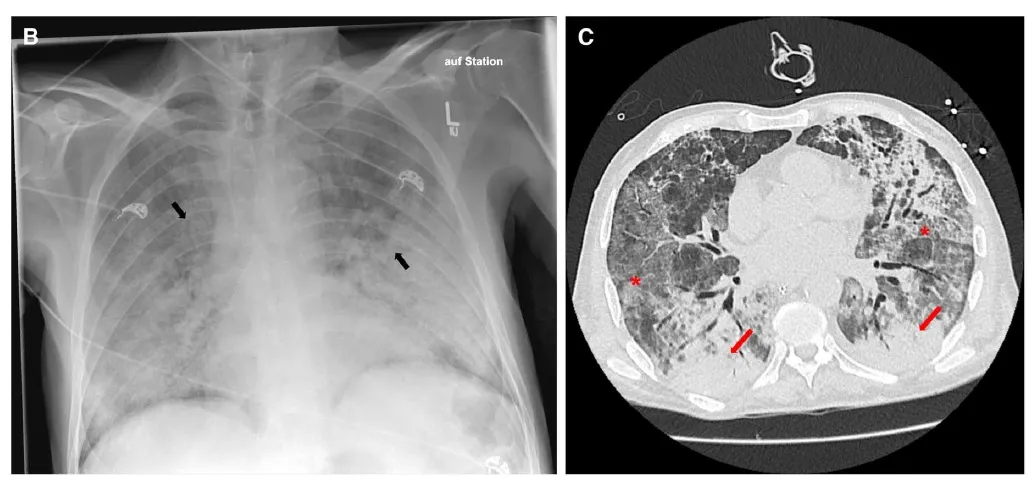

Paciente com IRA associada a Inibidores de Checkpoint

Paciente com IRA associada a Inibidores de CheckpointCaso interessante para quem avalia pacientes oncológicos, sempre ficar atento aos efeitos adversos relacionados ao tratamento quimioterápico

Valkercyo Feitosa